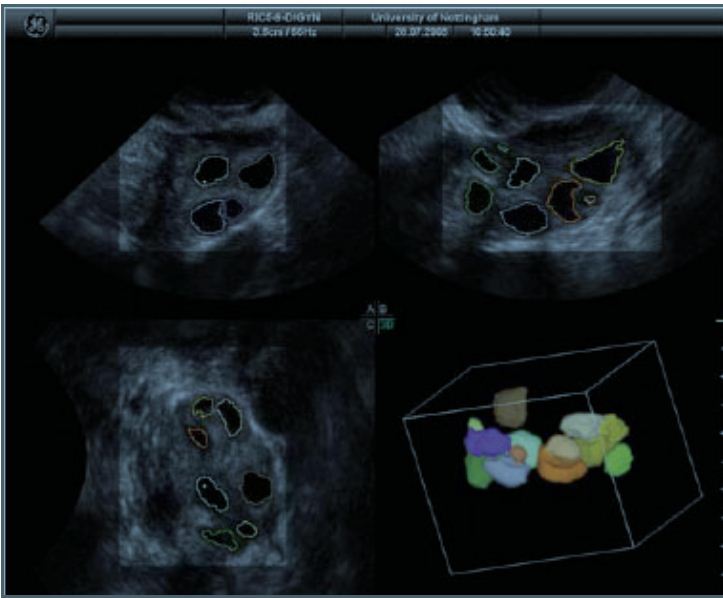

Since a woman's chronological age is the single most important factor in predicting a couple's reproductive potential, age has often guided infertility treatment choices. However, age alone doesn't tell the whole story, as women are different with their ovarian reserve even if they are of the same age. Determining ovarian reserve depend on measuring AMH (which is the most accurate way available) read more as well as ovarian morphological assessment using transvaginal ultrasonography.